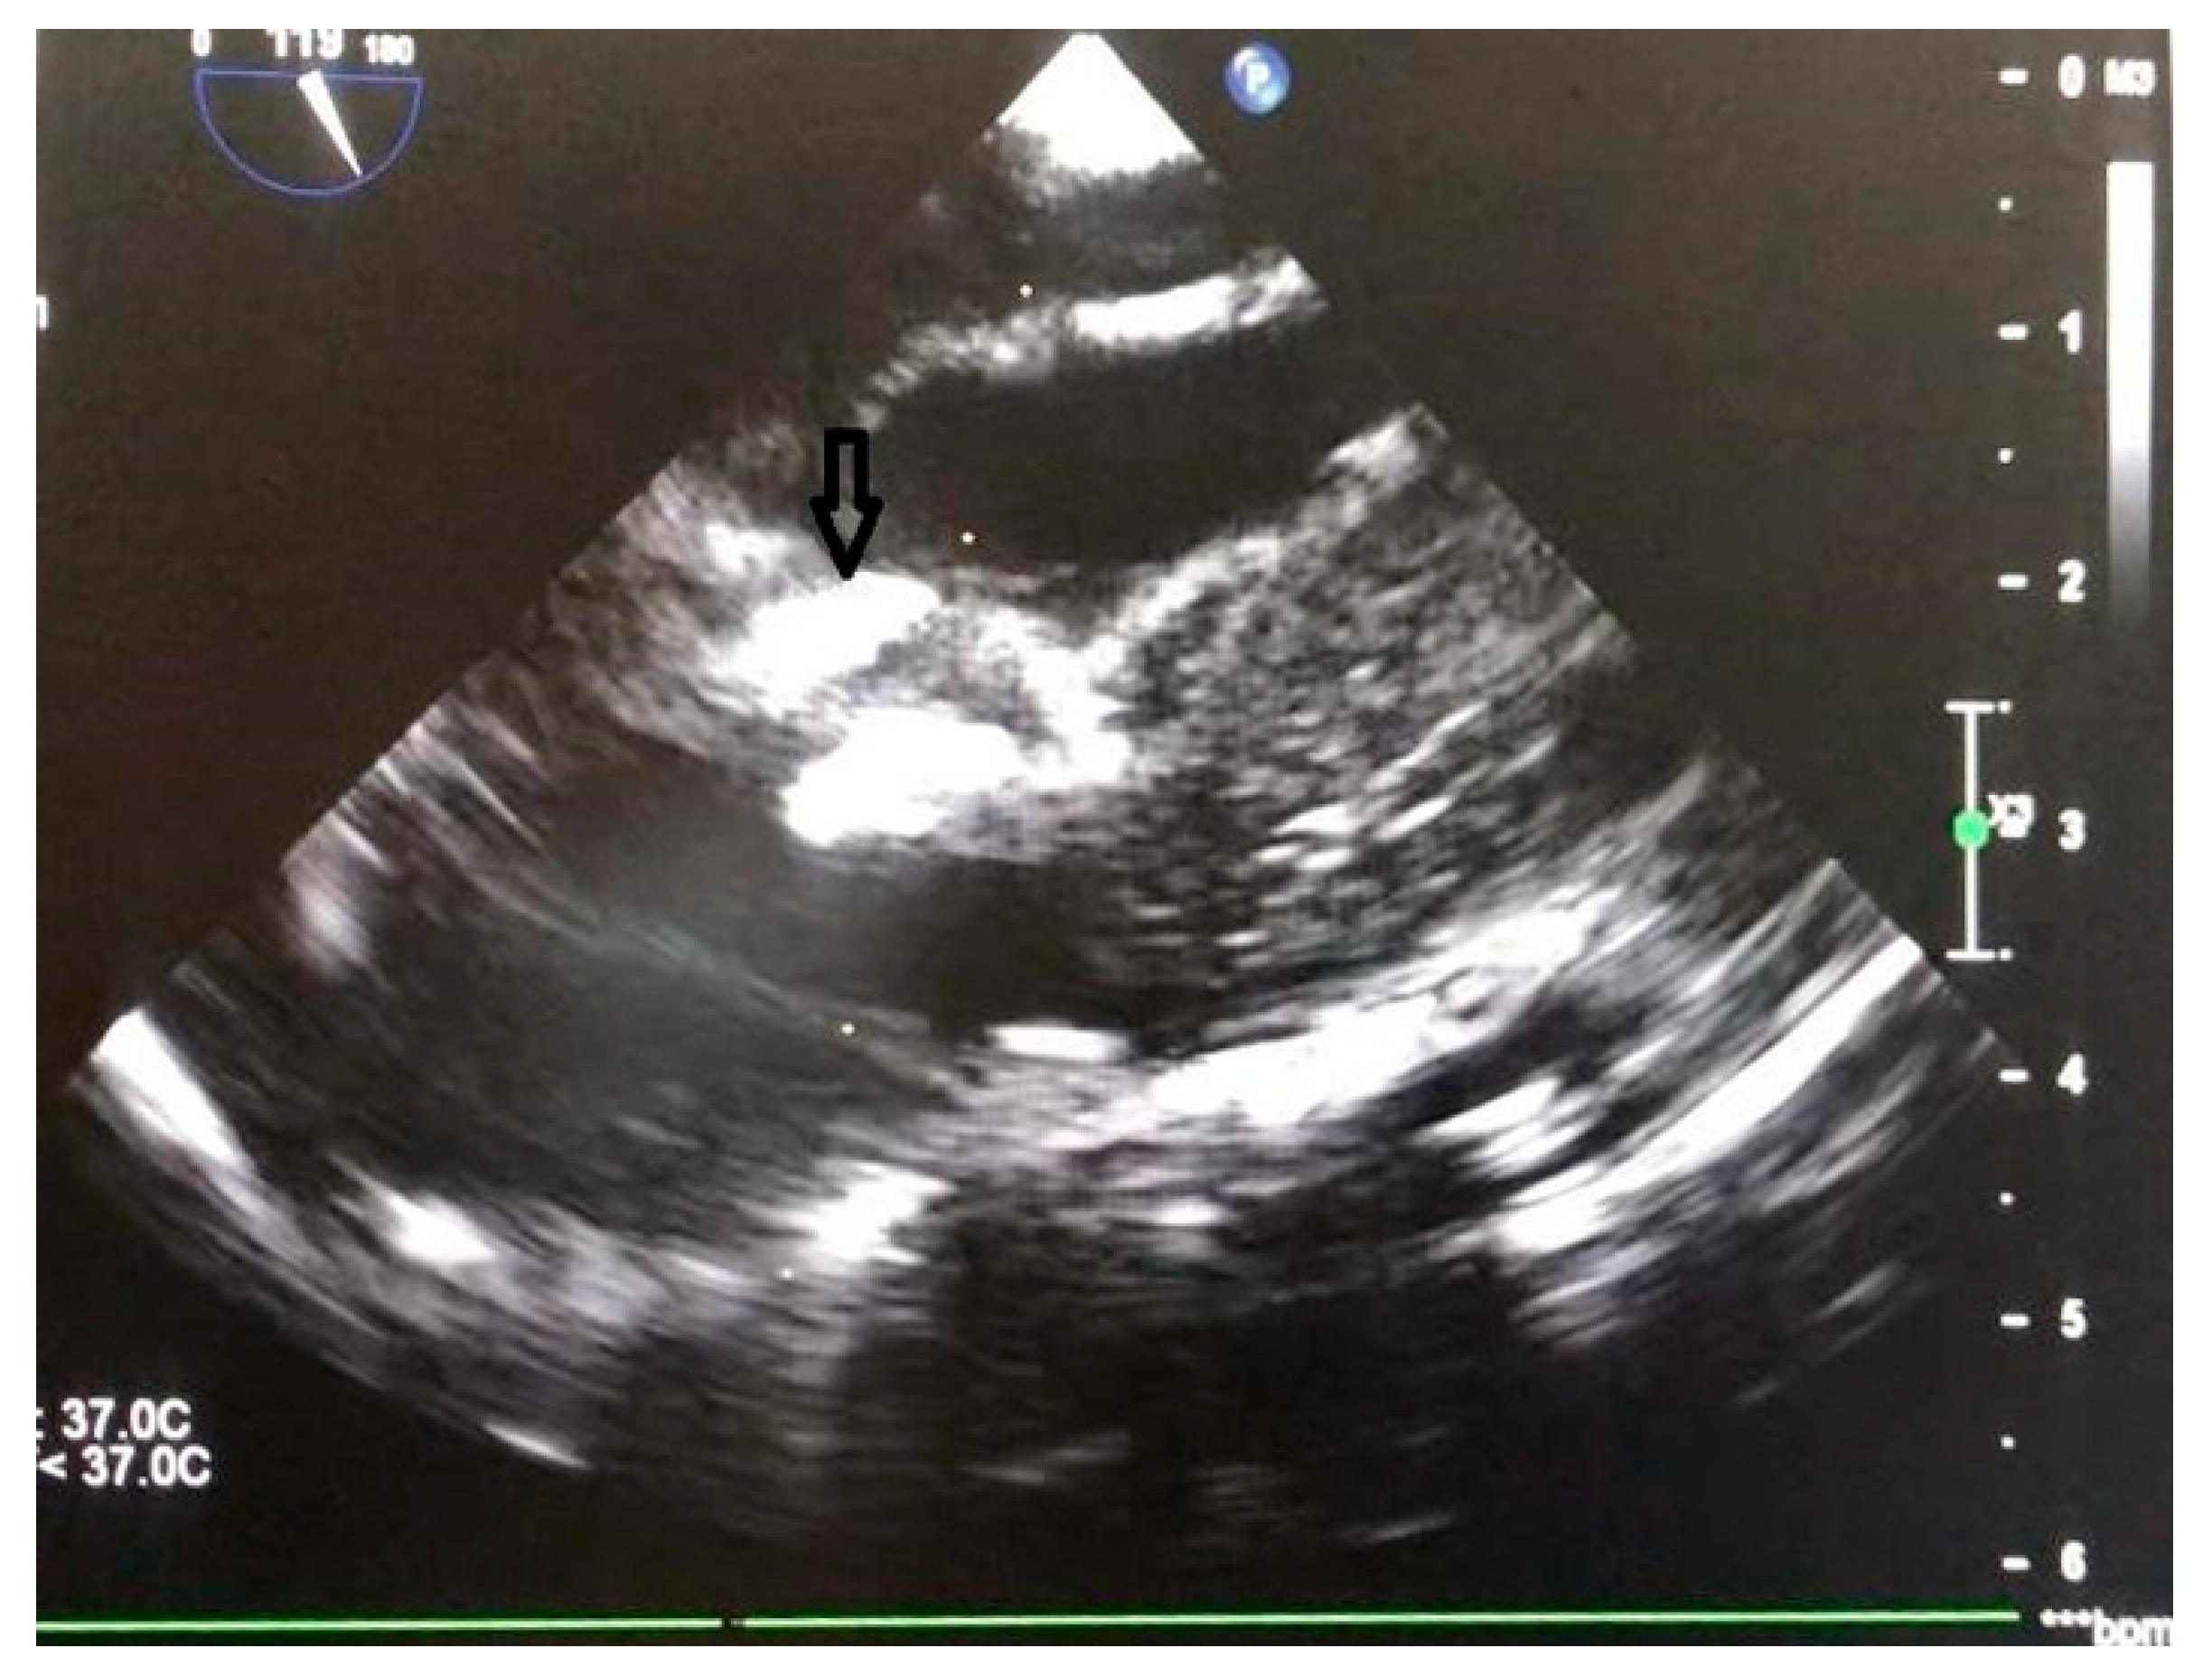

- Huang, L.L.; Chen, M.; Zeng, C.; Su, C.X.; Jiang, C.L.; Zheng, B.S.; Wu, J.; Li, S.K. Comparison of perventricular and percutaneous ultrasound-guided device closure of perimembranous ventricular septal defects. Front Cardiovasc Med 2023, 10, 1281860. [Google Scholar] [CrossRef]